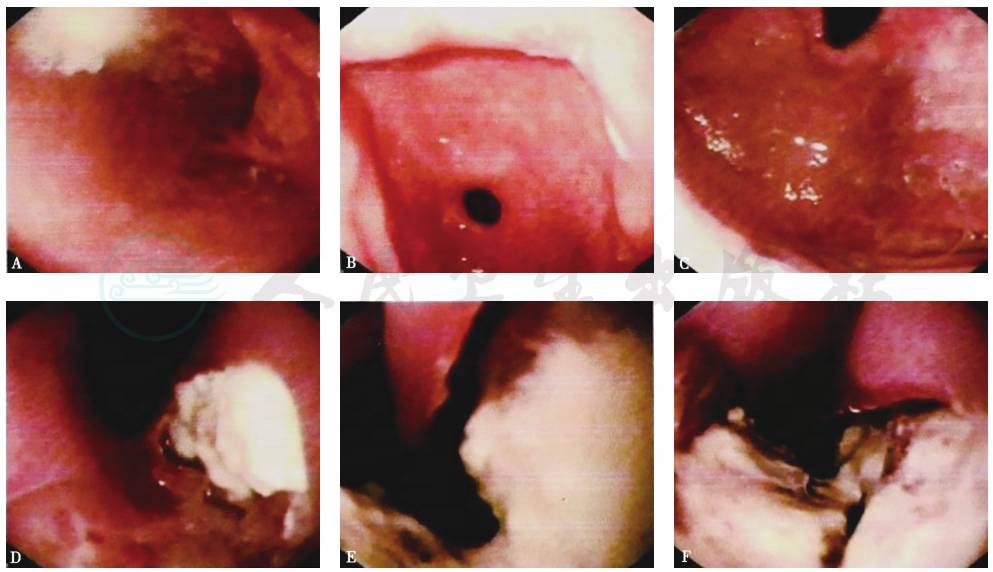

支气管镜下见:左侧声带固定,活动不良;气管下段、右主支气管、左主支气管黏膜肿胀、增厚,表面凹凸不平;左主支气管中段外后壁疑见一约长1cm的瘘口,可能为左主支气管-食管瘘(图3)。

活检(左主支气管)病理结果:慢性化脓性炎症,肉芽组织增生(图4);特殊染色PAS阴性,消化PAS阴性。

图3 支气管镜检查镜下表现

A.气管隆嵴;B.右主支气管;C、D、E.左主支气管;F.左上下叶开口